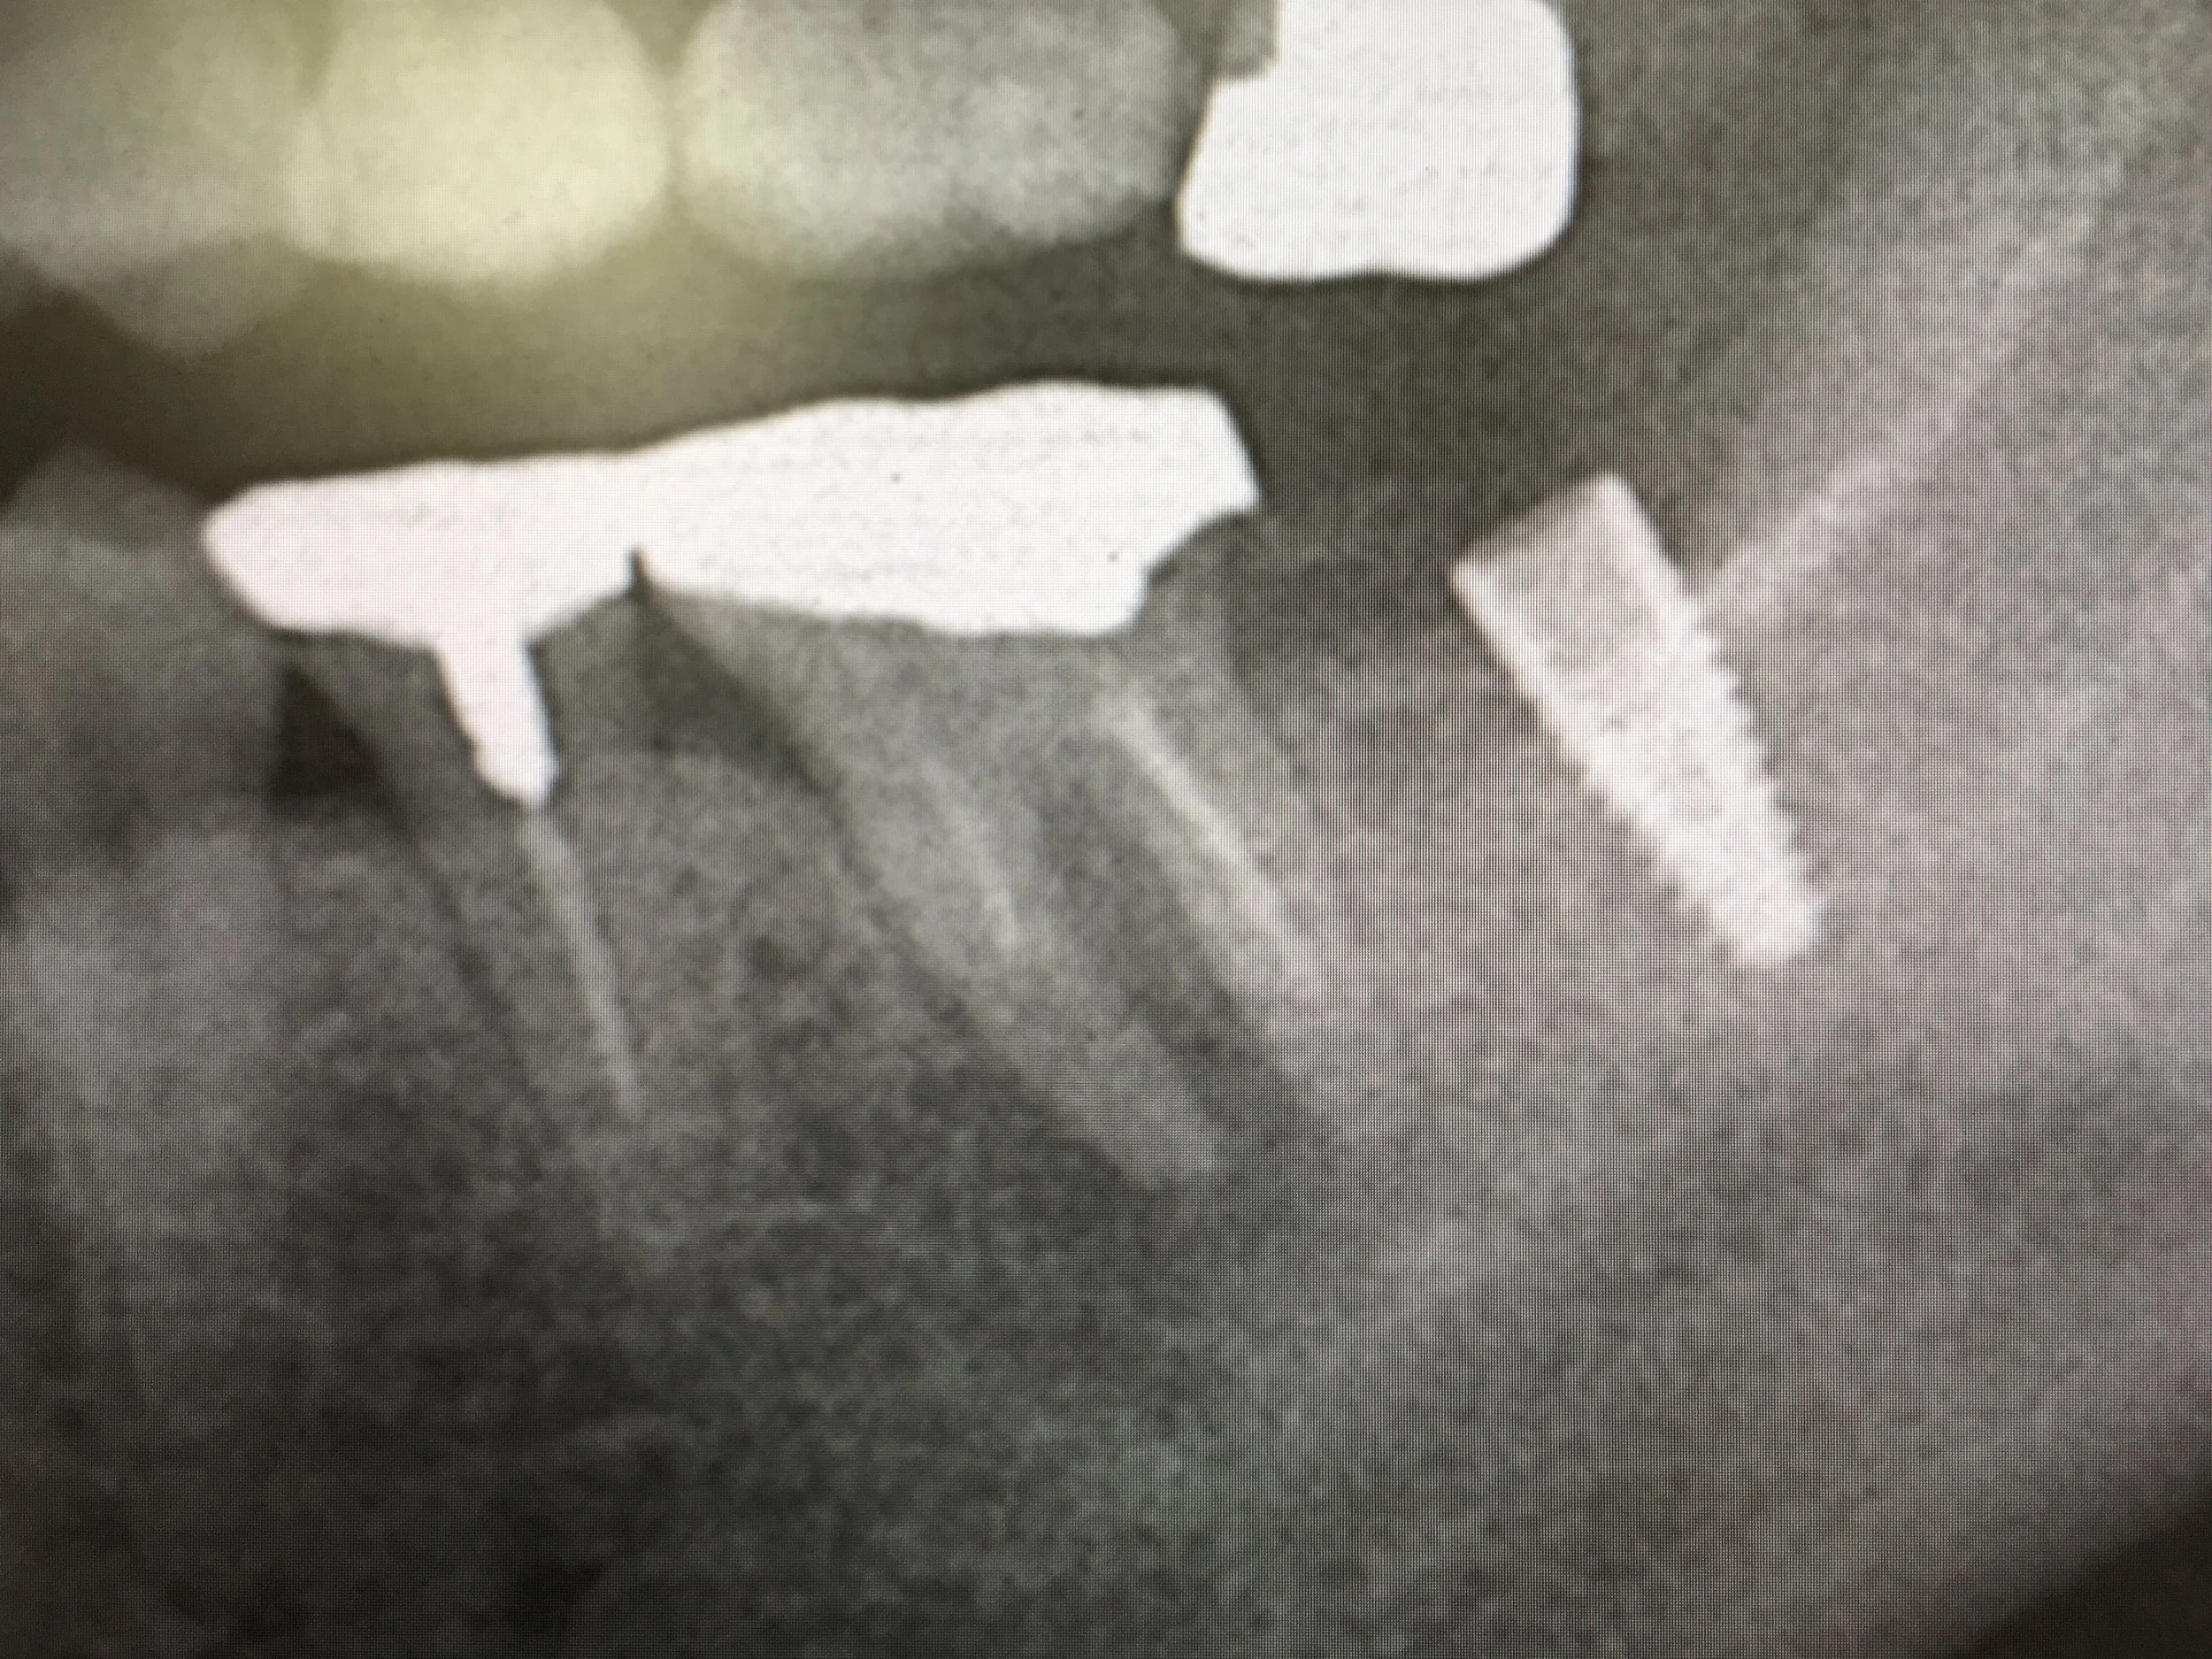

今日のインプラント

左下のインプラントは約一年経ちました。予後良好ですね。手前の歯の炎症も収まった様です。やはり全ての歯が揃っている事が大切なんですね。